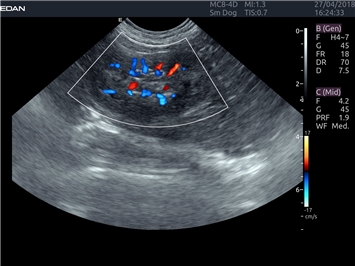

EDAN Acclarix LX4 VET представляет собой профессиональную ультразвуковую систему, специально разработанную для ветеринарных исследований. Сочетание стабильности, высокой производительности и эффективности делает эту систему идеальным выбором для современной ветеринарной практики.

Энергетический допплер:

Да

Цветовой допплер: